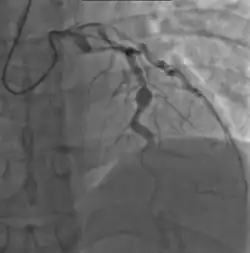

- Angiography was historically used to detect coronary artery aneurysms, and remains the gold standard for their detection, but is rarely used today unless coronary artery aneurysms have already been detected by echocardiography.